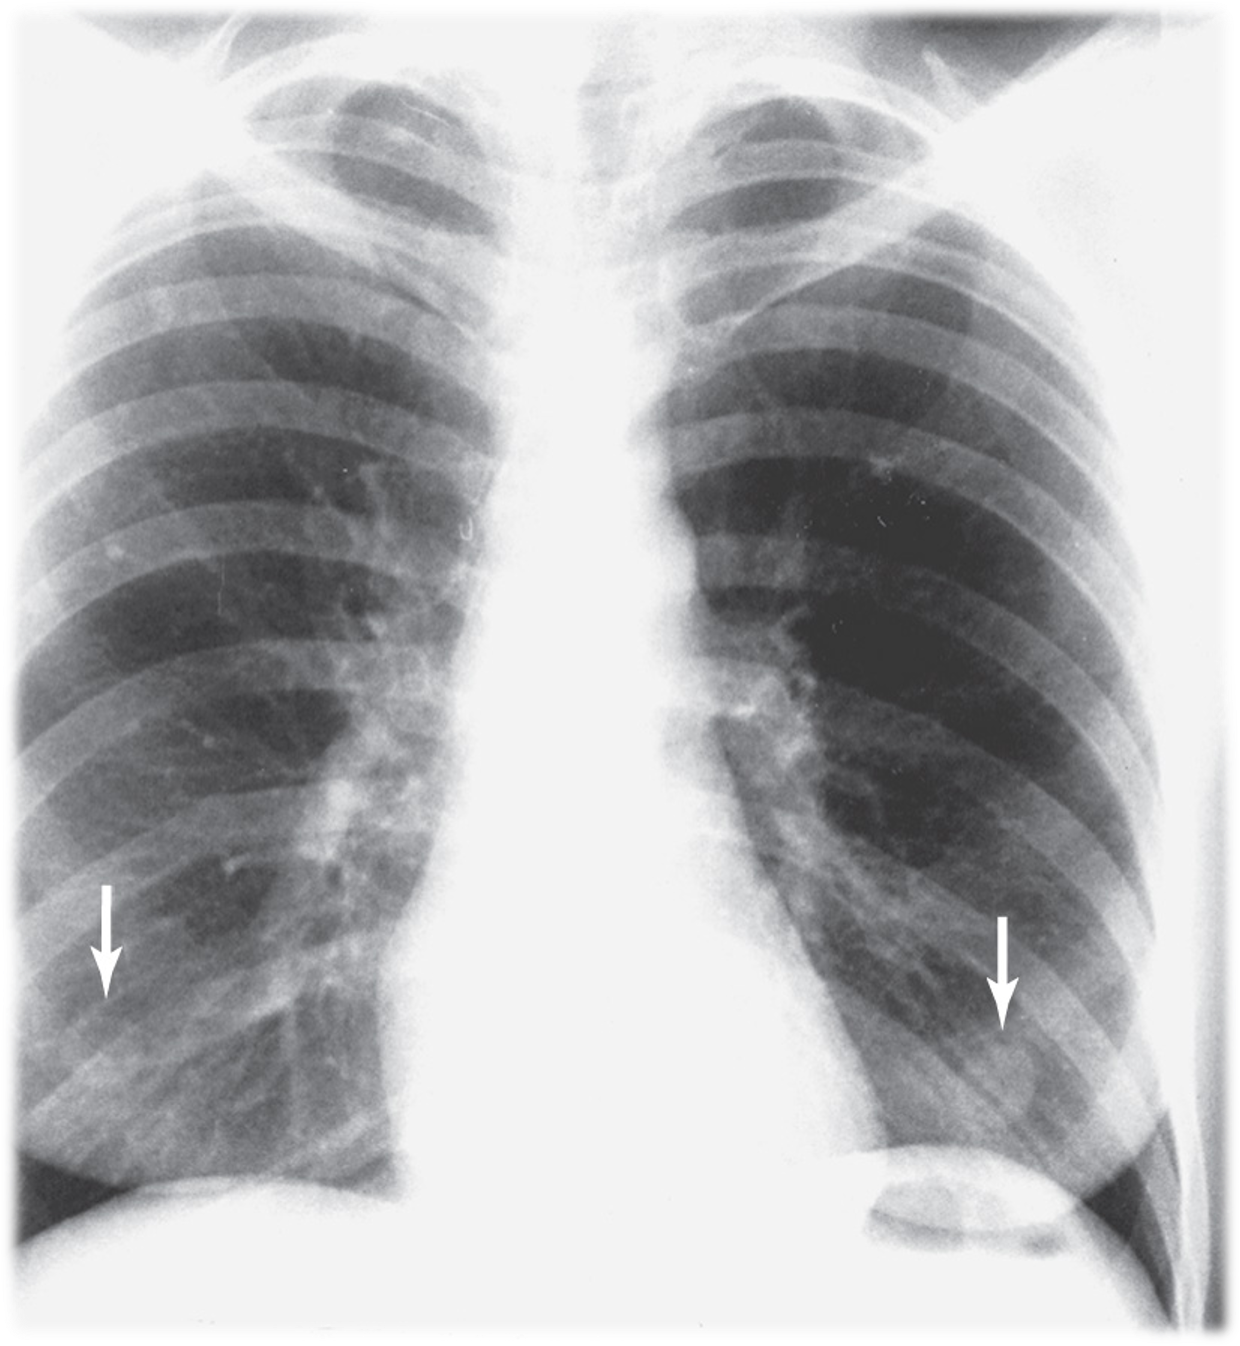

Differentiate between Kerley A vs Kerley B lines.

Kerley A: linear opacities extending from periphery to hila

Kerley B: small, horizontal, peripheral lines seen at the lung bases (represent thickened interlobular septa on CXR)

Interstitial infiltrate pattern on CXR found in patients with interstitial pulmonary edema?

Kerley lines